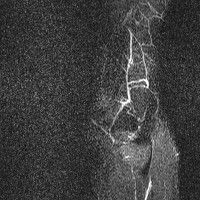

무릎 mri 간단히 봐주실 수 있으시나요 ㅠㅠ

안녕하세요 8년전 십자인대 수술하고 최근 무리한 운동에 무릎 불편감이 생겨서

mri 찍었습니다.

진단결과는 첫 찍은 병원에서 활액막염 이라는 진단을 받았습니다. 혹시 봐주실 수 있으실까요?

올라온 MRI가 단편적이라서 정확한 진단에 어려움이 있지만 십자인대에는 큰 이상이 있지는 않은것 같으며, 무릎관절내 물이 있는 것으로 보아 활액막염의 진단이 맞을 것 같습니다.

하지만 단편적인 영상이기 때문에 촬영병원에서 정확한 판독지 등을 받으시는 것이 좋겠습니다.